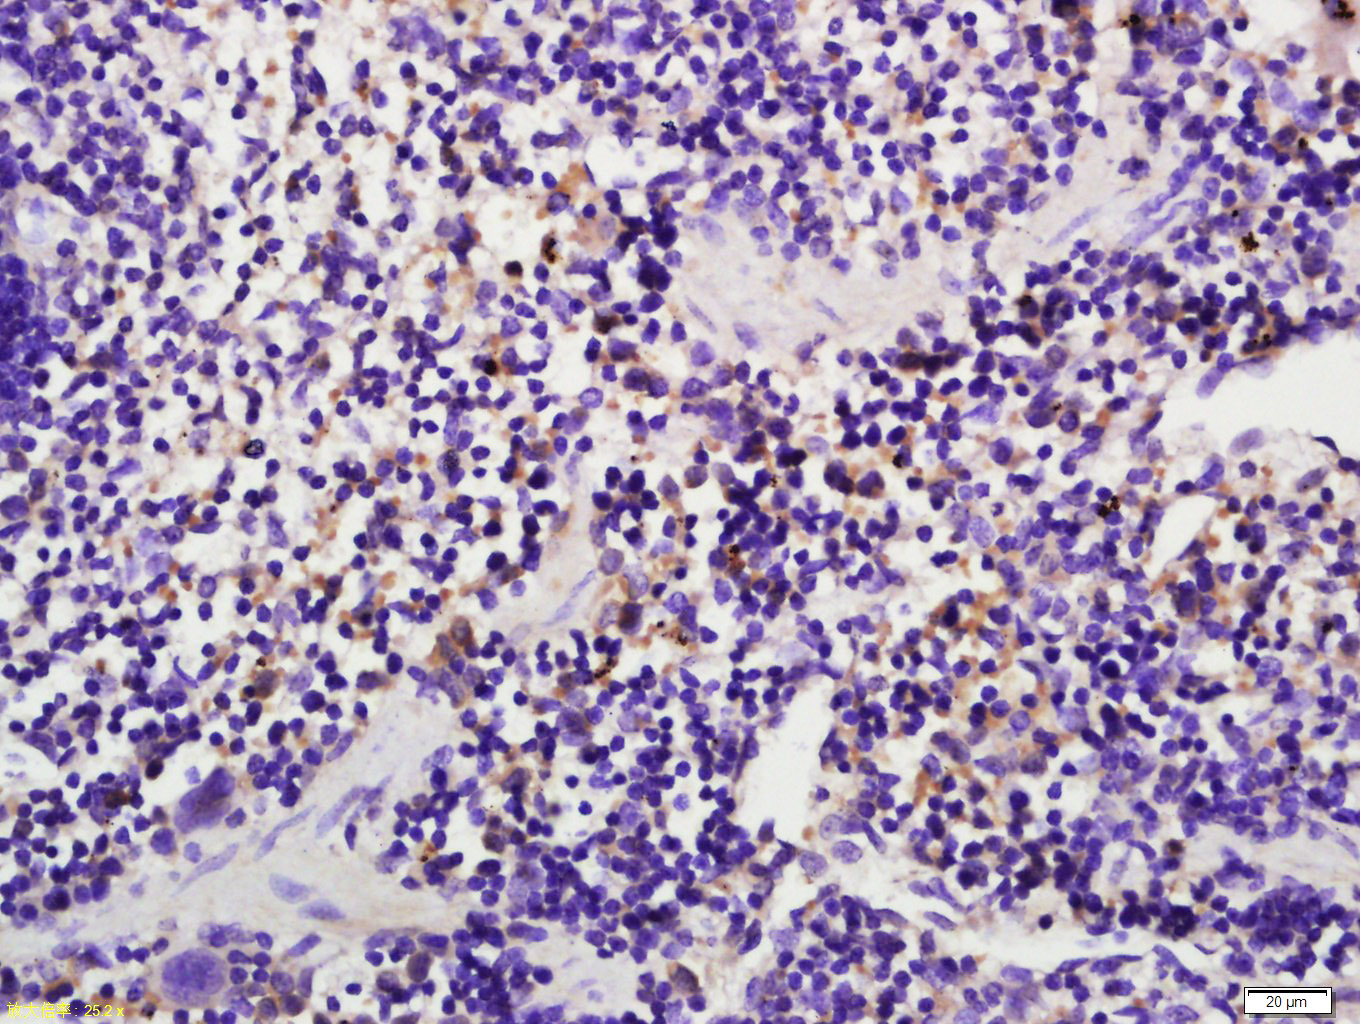

Tissue/cell: Mouse spleen tissue; 4% Paraformaldehyde-fixed and paraffin-embedded; Antigen retrieval: citrate buffer ( 0.01M, pH 6.0 ), Boiling bathing for 15min; Block endogenous peroxidase by 3% Hydrogen peroxide for 30min; Blocking buffer (normal goat serum,C-0005) at 37∩ for 20 min; Incubation: Anti-Caspase-1 p20 Polyclonal Antibody, Unconjugated(bs-10442R) 1:500, overnight at 4∑C, followed by conjugation to the secondary antibody(SP-0023) and DAB(C-0010) staining